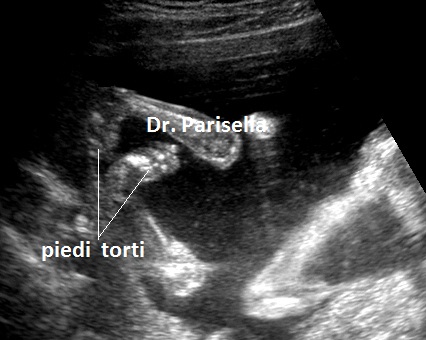

E' una malattia genetica rara caratterizzata da lussazione congenita poliarticolare tra cui il Congenital Genu Recurvatum (bilaterale), piede torto, mano torta e caratteristica facies caratterizzata da ipertelorismo, radice del naso depressa, bozza frontale prominente, micrognazia e palatoschisi.